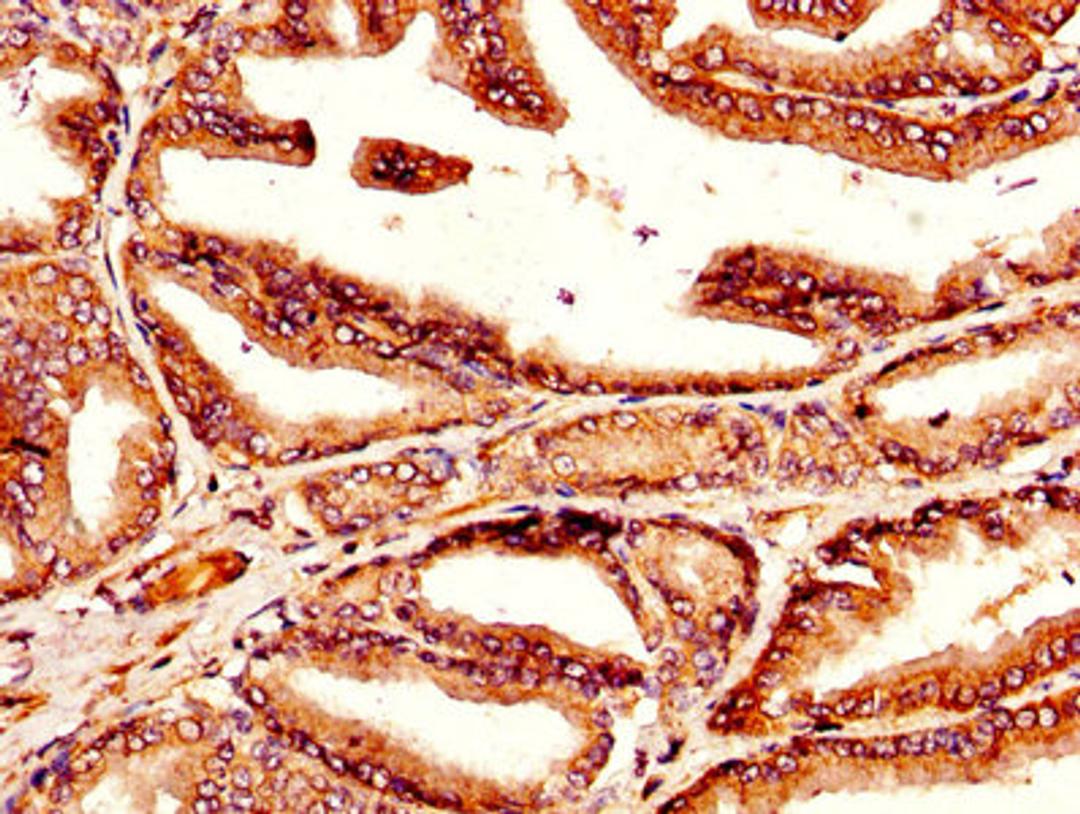

IHC image of CSB-PA023464LA01HU diluted at 1:300 and staining in paraffin-embedded human prostate tissue performed on a Leica BondTM system. After dewaxing and hydration, antigen retrieval was mediated by high pressure in a citrate buffer (pH 6.0). Section was blocked with 10% normal goat serum 30min at RT. Then primary antibody (1% BSA) was incubated at 4°C overnight. The primary is detected by a biotinylated secondary antibody and visualized using an HRP conjugated SP system.